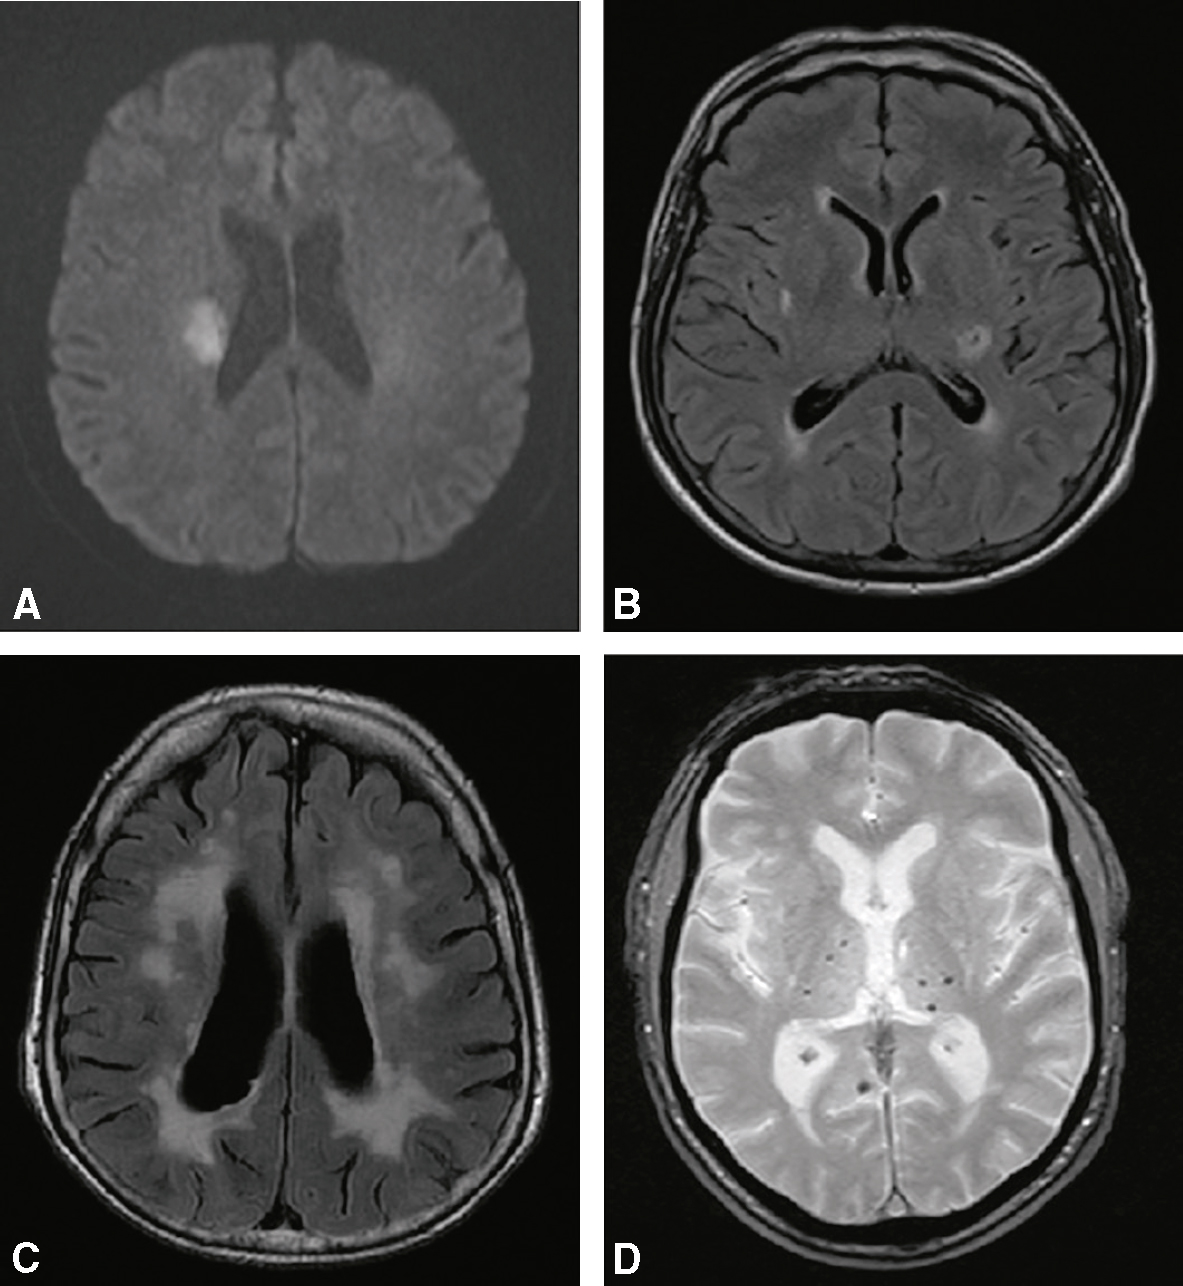

3 520Petits infarctus profonds ou « lacunes » (fig. 28.6)

Fig. 28.6 Figure Microangiopathie cérébrale.

A. Infarctus lacunaire récent (IRM séquence de diffusion) hémisphérique droit. B. Infarctus lacunaire ancien (IRM séquence FLAIR). C. Leucoencéphalopathie vasculaire (IRM séquence FLAIR). D. Microbleeds (microsaignement) (IRM séquence T2*).

• Figure Conséquence d’une occlusion d’une artériole perforante (diamètre de 200 à 400 urn).

• • 521Figure Des tableaux cliniques évocateurs divers peuvent révéler ces petits infarctus. Les plus fréquents sont :

• – hémiplégie/hémiparésie pure (capsule interne ou tronc cérébral);

• – hémianesthésie pure d’un hémicorps ou à prédominance chéiro-orale (thalamus);

• – hémiparésie + hémi-hypo-esthésie (tronc cérébral);

• – dysarthrie + main malhabile (bras postérieur de la capsule interne ou pied de la protubérance);

• – hémiparésie + hémiataxie (protubérance ou substance blanche hémisphérique).

• • La fluctuation à la phase initiale de l’intensité des manifestations cliniques mentionnées ci-dessus est évocatrice de ce type d’infarctus.

• • L’état « multilacunaire » est la conséquence de la multiplication des petits infarctus profonds. Il est caractérisé par l’association de :

• – syndrome pseudo-bulbaire, troubles de la déglutition et de la phonation (voix nasonnée);

• – rires et pleurs spasmodiques;

• – marche à petits pas (évoquant un syndrome parkinsonien atypique);

• – troubles sphinctériens;

• – détérioration des fonctions cognitives.

2 Microangiopathies (fig. 28.6)

a Infarctus dits « lacunaires »

• Figure Environ 20 % de l’ensemble des infarctus cérébraux.

• Figure Petit infarctus profond de moins de 20 mm de diamètre en séquence de diffusion.

• • 526Liés à l’occlusion d’une artériole profonde sur artériopathie locale dont le principal facteur de risque est l’HTA.

• • Localisation préférentielle des infarctus « lacunaires » :

• – noyaux gris centraux;

• – capsule interne (bras postérieur);

• – pied du pont (ou protubérance) .

• • On suspecte un infarctus lacunaire chez un patient hypertendu en cas de tableau clinique évocateur (voir plus haut).